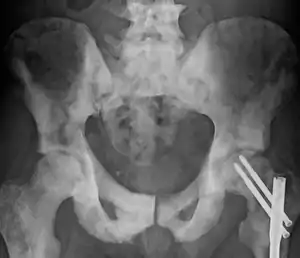

Sclerosis of the bones of the pelvis due to prostate cancer metastases